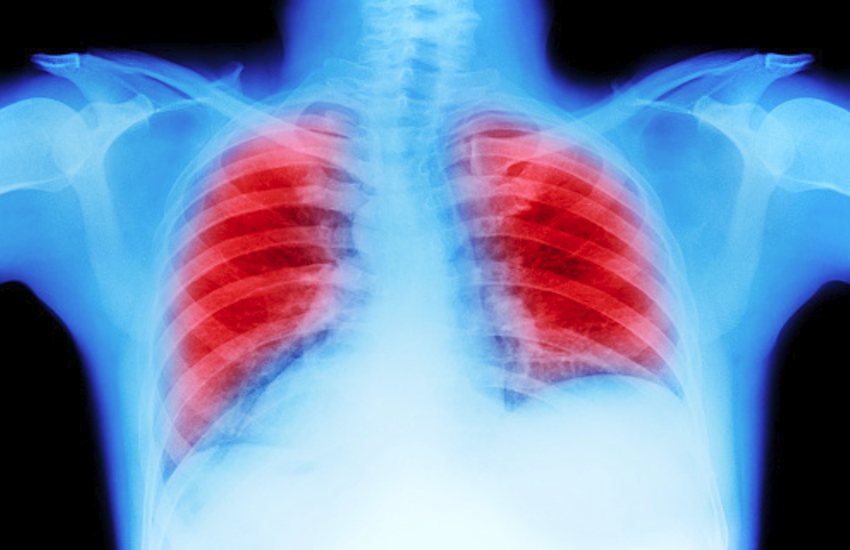

Lung Carcinoma In Hindi: फेफड़े के कैंसर को लंग कार्सिनोमा भी कहते हैं। इसमें कैंसर कोशिकाएं अनियमित रूप से एक या दोनों फेफड़ों में विकसित होने लगती हैं। इस रोग के ज्यादातर मामले धूम्रपान करने वालों में सामने आते हैं। रोग की शुरुआत में अनियमित रूप से बढ़ने वाली कोशिकाएं ट्यूमर का रूप लेने लगती हैं और फेफड़ों के काम यानी रक्त के जरिए पूरे शरीर में ऑक्सीजन पहुंचाने, को बाधित करती हैं। जानते हैं रोग के लक्षण और इलाज के बारे में-

1. प्राइमरी स्टेज : चेस्ट एक्स-रे और सीटी स्कैन।